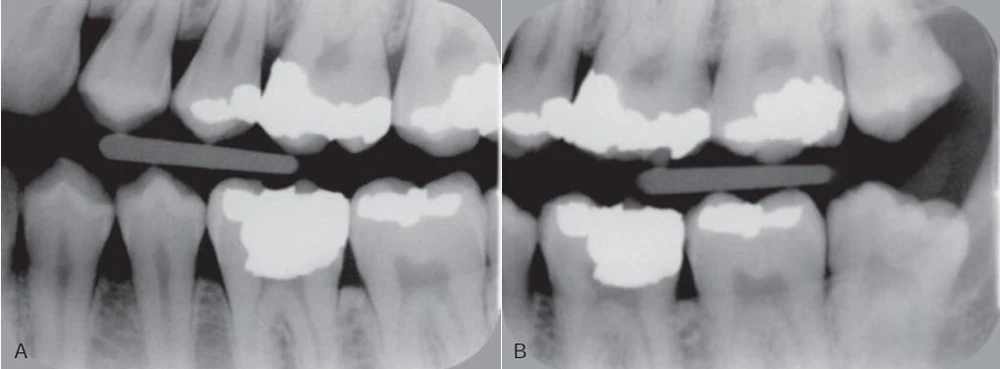

Hình 3. Phim cánh cắn phần hàm trái của bệnh nhân.

Hình 4. Phim cánh cắn ở bộ răng hỗn hợp cho thấy tổn thương sâu ngà ở mặt gần và xa răng cối sữa thứ hai và tổn thương men ở mặt gần răng cối lớn vĩnh viễn thứ nhất. Tổn thương lan rộng ở thân và chân răng cối sữa thứ nhất hàm dưới.

Những cân nhắc điều trị như việc tạo xoang trám thường không được chỉ định cho những tổn thương ở men răng và nha sĩ cũng như bệnh nhân có thể kiểm soát tiến triển của tồn thương bằng những can thiệp bản tồn. Mặt khác, với những tổn thương có lỗ thì cần tạo xoang trám. Trong trường hợp tổn thương ở ngà răng, quyết định liệu có trám răng hay không tuỳ thuộc vào mỗi bệnh nhân, cần theo dõi bằng X quang để đánh giá liệu tổn thương đã dừng lại hay đang tiến triển. Thời gian giữa các lần chụp X quang tuỳ thuộc vào mỗi các nhân, tiền sử sâu răng trước đây, tuổi và vị trí tổn thương vì tỉ lệ tiến triển khác nhau giữa những bề mặt răng khác nhau. Cần chụp lại một phim X quang có góc hình học giống với phim ban đầu bằng cách dùng cây giữ phim, giúp so sánh chính xác độ sâu của tổn thương giữa hai lần chụp theo dõi. Khi sử dụng phim kỹ thuật số cùng với góc hình học cũ, có thể để các hình ảnh chồng lên nhau và những thông tin trên một hình ảnh được loại trừ bởi một hình ảnh khác, cho ta một hình ảnh sau khi loại trừ xong – hình ảnh này hiển thị những thay đổi đã xảy ra giữa hai lần kiểm tra.

Một tổn thương tiến triển cho thấy cần trám lại. Với những bệnh nhân tích cực làm sạch bề mặt răng và sử dụng liệu pháp fluoride, hơn một nửa tổn thương ngà nông có thể ngừng lại, vì vậy có thể tránh liệu pháp phục hồi.